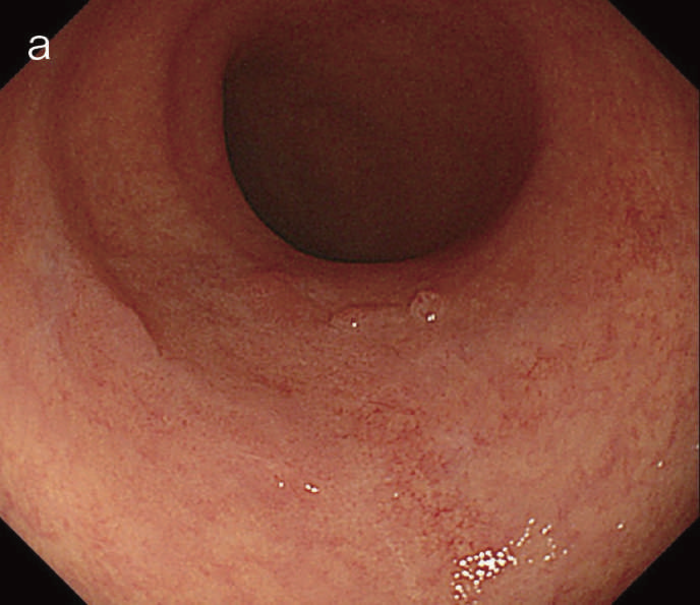

図6 UC関連LGDの内視鏡所見

- 白色光像:直腸(下部直腸)に色調変化は乏しく,微小な隆起を複数認めた。背景粘膜は寛解期にあった。

- NBI非拡大像:Brownishな領域が明らかとなった。

- 色素内視鏡像:病変辺縁が明瞭な微小な隆起を複数伴う表面平坦型病変。

- NBI拡大像:口径整でらせん状の微小血管と絨毛状の表面構造を認めた。

- pit pattern像:小型の類円形,管状pitを認めた。